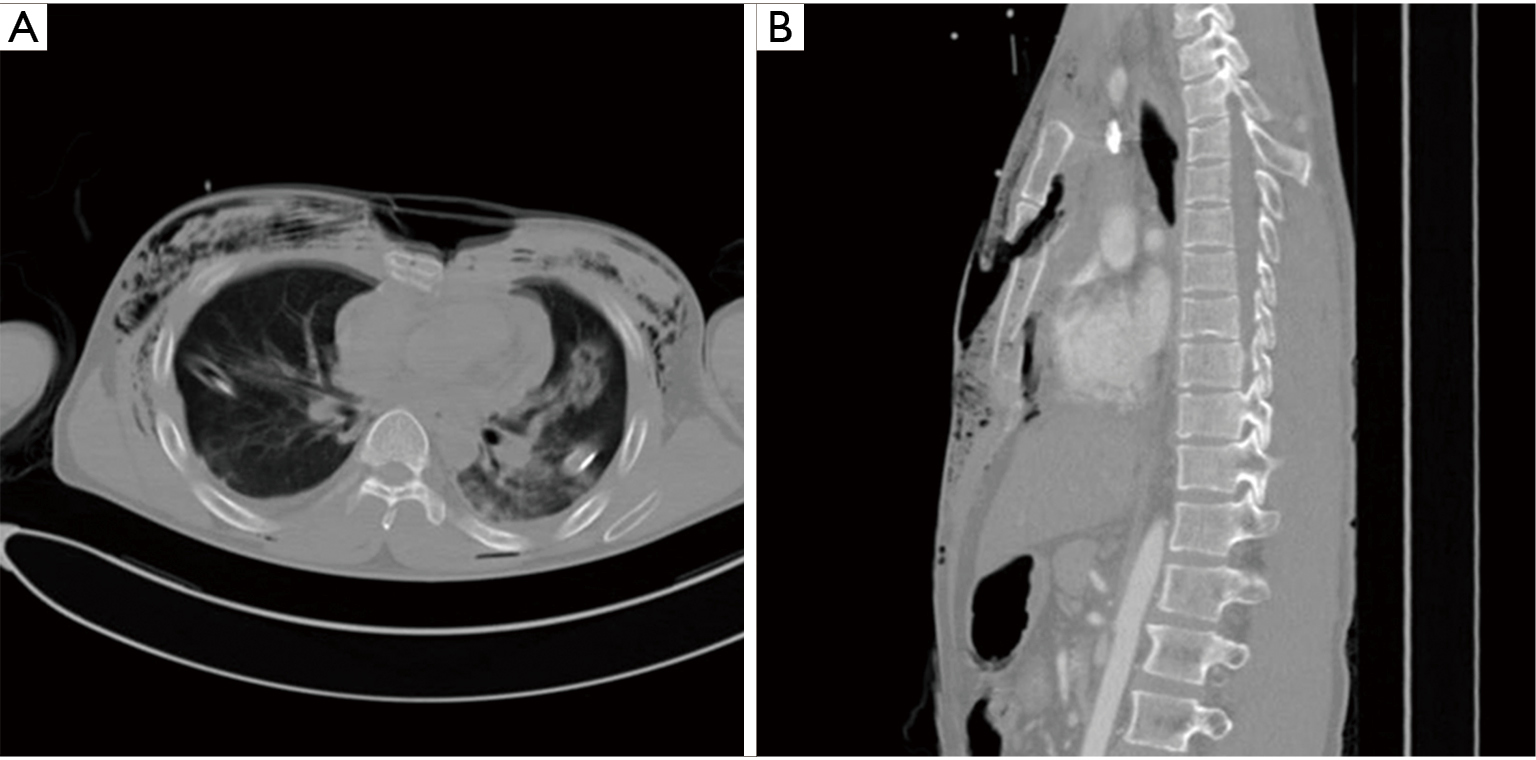

From docslib.org

Nuss Procedure for Surgical Stabilization of Flail Chest with Flared Ribs After Nuss Procedure I had nuss procedure in 2016 and after 2.5+ years the bar was removed. The nuss procedure is a popular minimally invasive technique that involves placing a bar behind the sternum to push it. In this blog post, you'll learn what causes flared ribs, how to identify them, and the best exercises and tips to correct them. This is where. Flared Ribs After Nuss Procedure.

From www.semanticscholar.org

Figure 2 from Nuss procedure for surgical stabilization of flail chest Flared Ribs After Nuss Procedure Because more adults are undergoing pectus repair with the nuss procedure, an understanding of a potentially increased risk is necessary. The nuss procedure is a popular minimally invasive technique that involves placing a bar behind the sternum to push it. I hope i'm imagining this but has anyone experienced rib flare getting worse after the nuss procedure? This is where. Flared Ribs After Nuss Procedure.

From jtd.amegroups.com

Nuss procedure for surgical stabilization of flail chest with Flared Ribs After Nuss Procedure Whether it's due to posture, muscle imbalances, or something else, i'll guide you through the most effective strategies to correct it. It seems my belly is protruding out. Pectus excavatum is the leading cause of rib flare. Because more adults are undergoing pectus repair with the nuss procedure, an understanding of a potentially increased risk is necessary. I had nuss. Flared Ribs After Nuss Procedure.